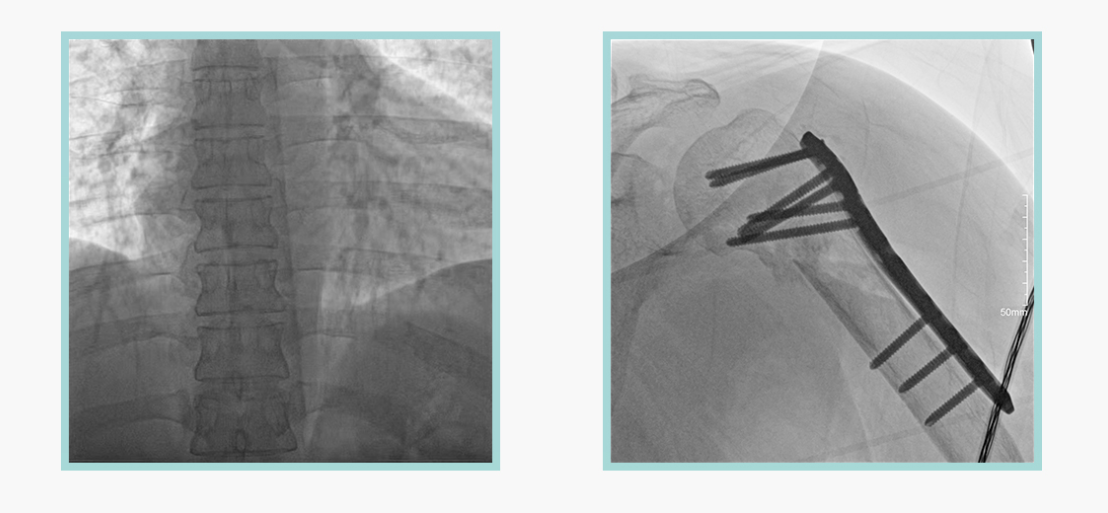

德赢VWIN科技悦画移动C臂X线摄影系统,采用了业内技术最尖端的CMOS探测器。基于性能优异的针状CSI闪烁体涂层和高灵敏度的CMOS感光芯片,悦画可以实现在超低X线剂量条件下实现高清晰影像成像,相较于一般的影增移动C臂和平板C臂,动态范围更高,影像的层次感和对比度更好。

在产品的性能参数设计上,悦画的像素可达到200万,空间分辨率可达到3.2线对,采用16bit的影像灰度,悦画在影像后处理上,通过SPI金字塔图像算法,支持摄影、脉冲透视影像、连续透视等多种模式下的影像采集,动态透视影像视频支持保存与回放。双大屏的设计,透视影像支持三档放大,保证临床影像读取的便利。

悦画在影像的伪影处理上,也积累多项图像处理专利技术。通过对植入物的精准识别,悦画能够精准祛除植入物伪影与运动伪影,保证高质量的影像输出,无论是影像的对比度、分辨率(清晰度)相较于市面上的移动C臂产品都更胜一筹。